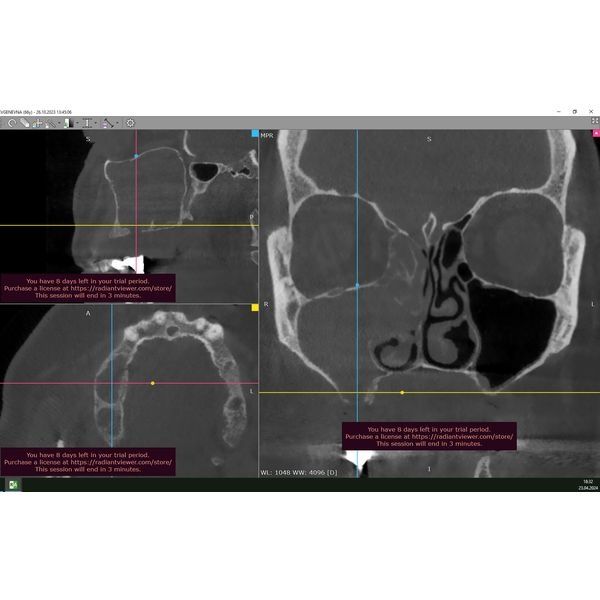

Была проведена конусно-лучевая томография головы. В ходе обследования определялись: обширный дефект мягких и твёрдых тканей верхней челюсти справа, тотальное затемнение верхнечелюстной пазухи (полное заполнение пазухи патологическим содержимым) с полипами и выделением содержимого в полость носа.